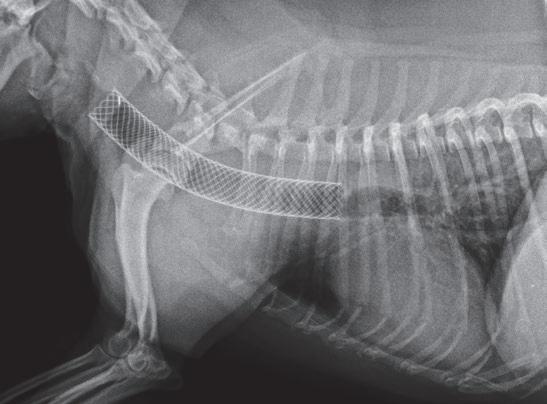

Agujas de acceso vascular